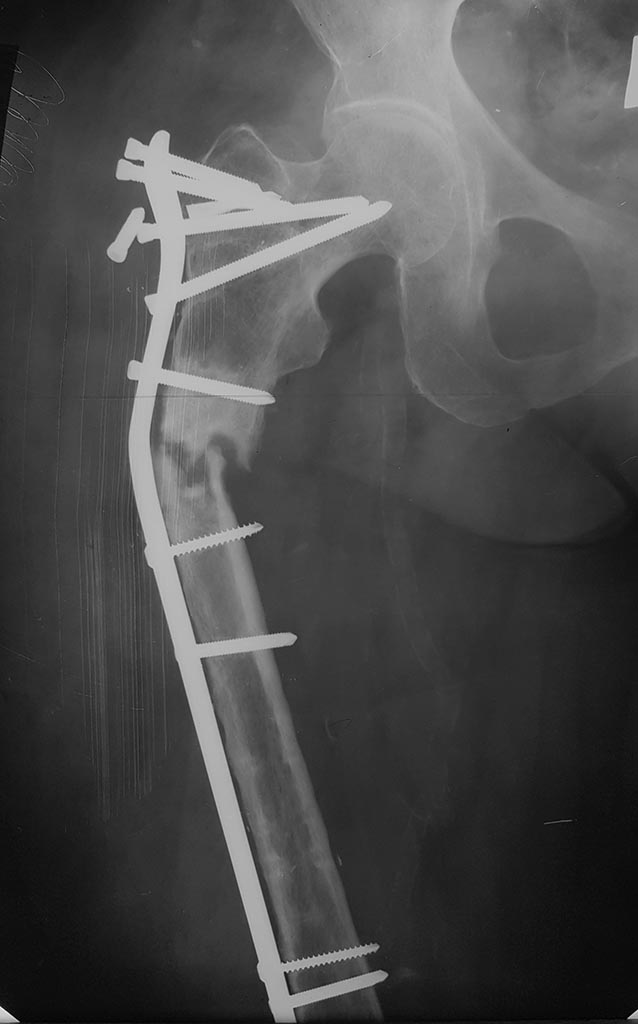

Операцию сделали, инфекции не выявлено, резецированы концы бедренной кости на 10 - 20 мм с каждой стороны, дистальный конец был нежизнеспособен, щели перелома выполнены губчатым аутотрансплантантом, также по передней поверхности фиксирован винтами губчато-кортикальный аутотрансплантант.

Дистального блокирования не видно. Один или два винта?

2 винта в метафизе

1. Операцию делали следующим образом: выполнена поперечная (на глаз) резекция дистального отломка до жизнеспособных (кровяная роса на опиле), но не "полумертвых" тканей, затем минимальная резекция проксимального отломка также поперечная (на глаз). После введения стержня и спирального винта увидели, что идеального сопоставления не получилось. Подскажите, как технически надо было добиться строго поперечной резекции -подпиливать кость на уже установленном стержне по медиальной и задней поверхностях, либо удалять, подпиливать кость и вновь устанавливать систему PFNa?

4. К сожалению, оставили легкий варус. Промахнулись с точкой введения стержня - хотелось медиальнее. Хотелось легкий вальгус. "Вальгус - друг, варус - враг" (для проксимального бедра).

5. Решили пойти путем ранней нагрузки (ходьба с тростью с нагрузкой до 50% веса тела). 2 винта в дистальном метафизе создают возможность самостоятельной динамизации. Выложим снимки через 6 недель.